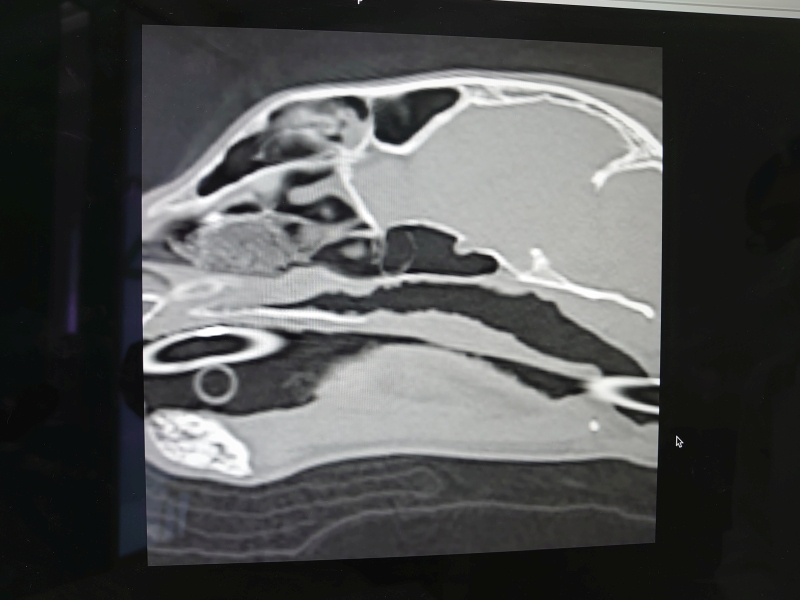

先生からCTと内視鏡の映像を見せてもらった

確かに先日見せてもらったワンちゃんの狭窄とは異なり、空洞は広いようだけど何かがへばりついてる..

先生の所見では今のところこれが炎症によるものなのか、リンパ腫なのかは判断できないとのこと..